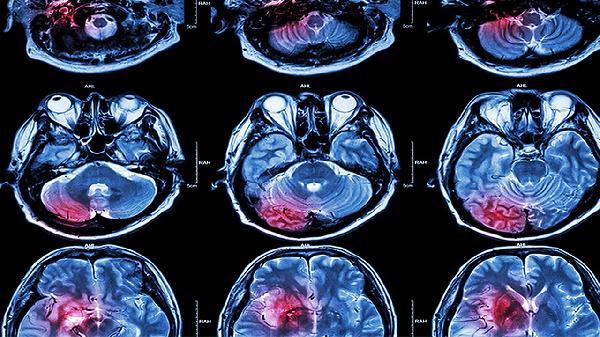

脑梗死患者的护理主要包括病情监测、康复训练、饮食调整、心理支持和预防并发症等方面。护理措施需根据患者的具体情况制定,以促进功能恢复、预防复发和提高生活质量。

密切监测患者的生命体征,包括血压、心率、呼吸和体温等。观察意识状态、肢体活动和语言功能的变化。定期复查血液指标和影像学检查,评估病情进展。发现异常情况及时告知医生,调整治疗方案。监测药物不良反应,确保用药安全。